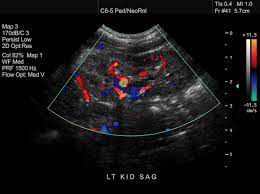

Your voice box sits just below your throat and also is susceptible to throat cancer. The symptoms and appearance of throat cancer depend on the specific part of the throat that is affected and the stages of its development. Throat cancer most often begins in the flat cells that line the inside of your throat. Ultrasound imaging can help determine the composition of lump, distinguishing between a cyst and a tumour. Ultrasounds are usually quick and most don't require special preparation. Throat cancer is a malignancy of either the tonsils, pharynx, or larynx. Your doctor will often use an ultrasound to create images of a fetus during pregnancy. Thyroid nodules are lumps that can appear in the thyroid gland in front of the throat. The ultrasound images are then projected onto a computer screen. A primary cancer of the lymphatic system is called lymphoma. Or, you might be told that you don't have cancer, based on an ultrasound, when in fact you do. Needle biopsy is only indicated if there is a mass within the thyroid goiter which is suspicious for malignancy. It can detect abnormal tissues, growths, and cysts and give a suspicion of cancer based on how those images look.

A thorough and accurate cancer diagnosis is the first step in developing a throat cancer treatment plan.at cancer treatment centers of america® (ctca), our experts use a wide range of tools and technologies designed for diagnosing throat cancer and evaluating the disease, with an emphasis on speed to care and timely results. Ultrasounds are usually quick and most don't require special preparation. A small device called a transducer is moved over the area. This test will usually help determine that the nodule has a low chance of being cancerous (has characteristics of a benign nodule), or that it has some characteristics of a cancerous nodule, and therefore a biopsy is indicated. It can detect abnormal tissues, growths, and cysts and give a suspicion of cancer based on how those images look. Your throat is a muscular tube that begins behind your nose and ends in your neck. The initial stage of throat cancer will start with vague and nonspecific symptoms and later it will start developing into unresolved lump or growth. Ultrasound is used to see the thyroid gland and the lymph node of the neck.